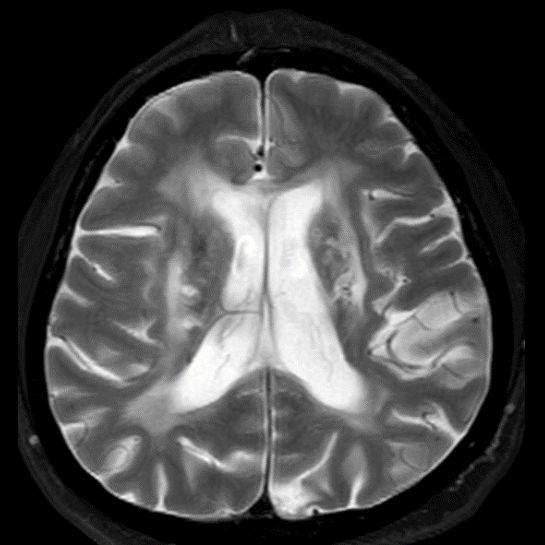

45 yaş, K

4 yıl önce akut sağ hemiparezi, konuşma bozukluğu ve dış merkezde serebellar iskemi tanısı ile ASA kullanımı öyküsü

Konuşma bozukluğu, yersiz gülme ve ağlama atakları, denge kaybı ve uyuşmaları devam ediyor